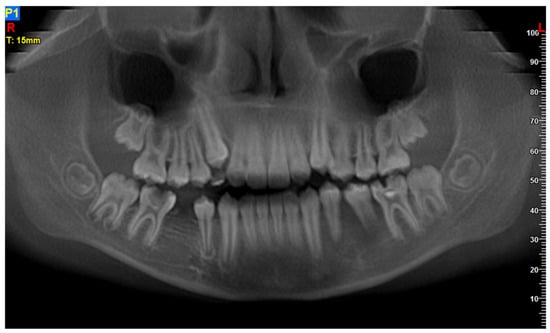

The 11-year-old patient was referred to the Children’s Dental Clinic with suspected inflammation of the periapical tissues of the region of the left premolar of the mandible. Clinical evaluation revealed hypermobility of teeth 34 and 35 (FDI) with enlargement and redness of gingival tissue of both the vestibular and lingual side of the alveolus with pain symptoms. Teeth with no signs of caries lesions were not tender to percussion, the vitality tests were inconclusive, and no palpable lymphadenopathy was noticed. A cone beam computed tomography (CBCT) examination (NewTome 3G, QR Verona, Italy, 110 kV, 2 mA, 18 s) revealed root resorption of tooth 35 and an area of extensive demineralisation in the region of 33–36 with loss of trabecular bone pattern, destruction of buccal, and thinning of the lingual cortical plates (Figure 1, Figure 2 and Figure 3). On the basis of the clinical examination and the unusual features of the X-ray examination, the diagnosis was extended to include a biopsy of soft and hard tissue. A histological examination revealed Burkitt’s lymphoma. An extent examination using 2-deoxy-2-[fluorine-18] fluoro- D-glucose integrated with computed tomography (18F-FDG PET CT), magnetic resonance imaging (MRI), and ultrasonography (USG) revealed a disseminated tumour process with infiltrates in the left palatine tonsil, head of the pancreas, stomach wall, and right pleura. On the basis of the results of the extended examination and according to the European Intergroup for Childhood Non-Hodgkin Lymphoma (EICNHL-COG Inter-B-NHL-2010) therapeutic protocol, the patient was classified into the B-High therapeutic group, and a 7-day cytoreductive prephase COP (Encorton, Cyclophosphamide, and Vincristine) was initiated. After completing the prephase, significant regression of the primary lesion was observed. Subsequently, the patient completed two cycles of R-COPADM (Rituximab, Vincristine, Methotrexate 3 g/m2, Cyclophosamide, Doxorubicin, and Encorton) and two cycles of R-CYM (Rituximab, Encorton, Methotrexate, and Cytarabine) treatments. The patient responded well to treatment, and remission was achieved. Now, five years after initial diagnosis, he is undergoing regular check-ups, including dental examinations. The intraoral lesion resolved completely because of chemotherapy, and no surgical treatment was performed (except for initial biopsy taking).

Figure 1. Patient, 11 y.o.: 3D volumetric reconstruction from CBCT examination: vertical bone loss and cortical bone destruction in the region of teeth 34 and 35.